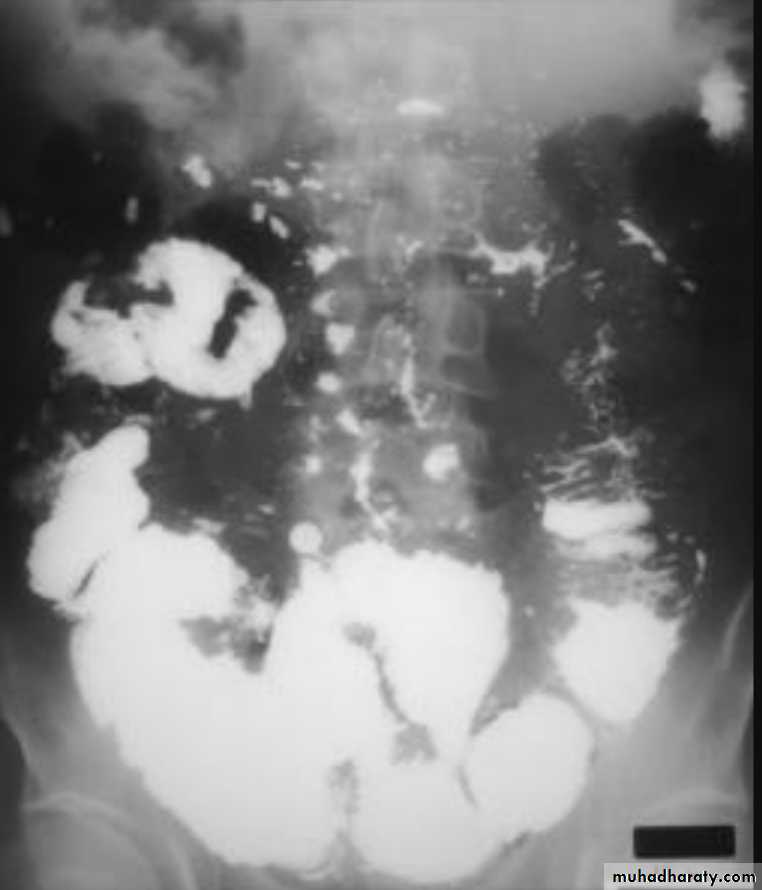

Ba examinationBarium studies of the small intestine Ba follow through Small bowel follow through (SBFT) routine investigation for delineation of all parts of the small boweldone with barium meal after having a quick look at esophagus, stomach, and duodenumRadiographic featuresOn a normal barium study of the small bowel, the jejunum is located in the upper left abdomen and the ileum in the lower right abdomen, to be continued by colon in ileo caecal region .The mucosa of the small bowel is characterized by the existence of the valvulae conniventes which give the small bowel normal feathery appearance in ba-follow through examination .

Barium small bowel follow-throughfindings of CD

Multiple mucosal ulcers aphthous ulcerslongitudinal fissures

Multiple skip lesions

when severe leads to cobblestone appearance

may lead to sinus tracts and fistulae

widely separated loops of bowel due to fibro-fatty proliferation

thickened folds due to edema

Pseudo diverticula formation: due to contraction at the site of ulcer with ballooning of the opposite site